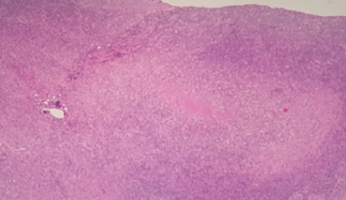

Cielo Gnecco, MS; Mary Hilal, MD; Daniel Sanchez, MD

A 42-year-old woman of Japanese descent presented with a 3-day history of a painful lump in her left neck.

08/29/2015